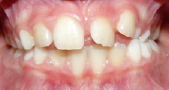

2 MORDIDA CRUZADA POSTERIOR

Mordida cruzada posterior: Los dientes posteriores superiores muerden por dentro de los inferiores. Se deben a un hueso maxilar (superior) estrecho y es importante corregirlas cuanto antes para que no afecte al desarrollo normal de ambos maxilares y evitar desviaciones esqueléticas de la mandíbula.